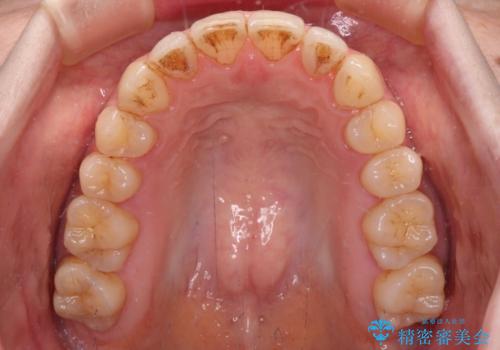

- 上下前歯の隙間を気にして来院された患者様です。

下顎前歯が1本欠損しており、上下小臼歯はクロスバイトとなり、上下前歯の接触もないという不正咬合の状態でした。

クロスバイトはワイヤー矯正が得意とするところであり、上下前歯の非接触や開咬はインビザラインの得意とするところであるので、ワイヤー装置により事前にクロスバイトを改善し、その後にインビザラインにて仕上げていくこととしました。

奥歯の咬み合わせに問題がある場合、インビザラインでは改善できないことが多々あります。事前にワイヤー装置により問題点を解消しておくことで、スムーズにインビザラインでの矯正治療を進めていくことができます。